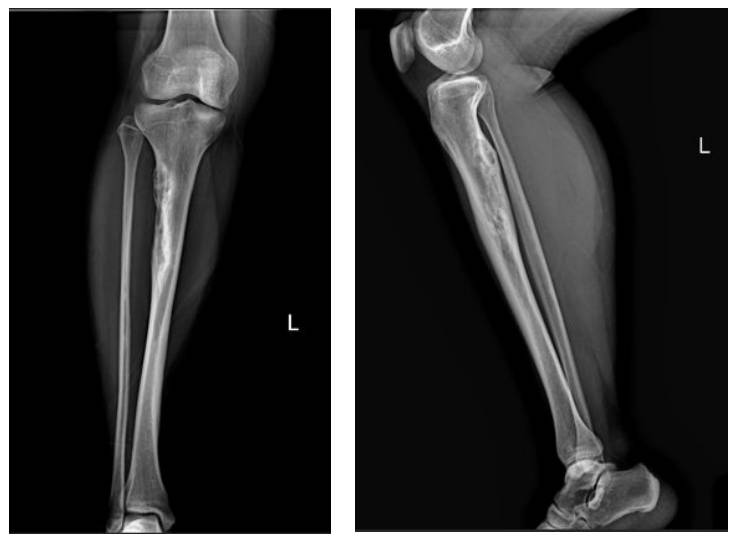

Ameliyat Öncesi: Röntgende proksimal tibia lateralde korteks harabiyeti ve düzensizlik görülmkte